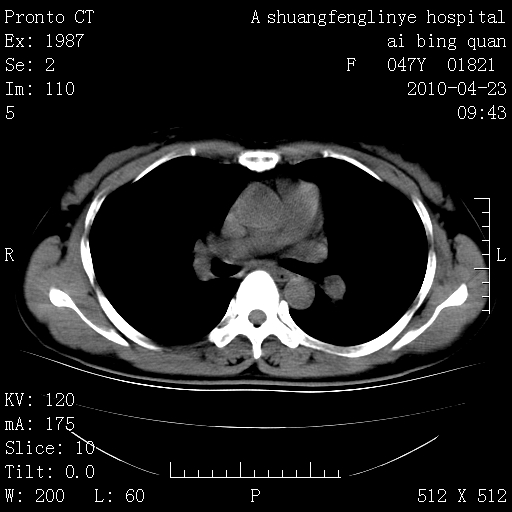

标题: CT25944:胸痛、气短、前几日高烧!肺Ca?请会诊! [打印本页]

标题: CT25944:胸痛、气短、前几日高烧!肺Ca?请会诊!

kaolv 周围型肺癌并同肺转移

双肺多发结节,考虑转移瘤,肺癌肺转移不除外

周围型肺癌并肺转移

左侧乳腺低密度灶

双肺多发结节,部分密度较高,最大结节边缘光滑。临床有“胸痛、气短、前几日高烧”病史。首选考虑:右肺感染性病变!建议积极消炎后复查!